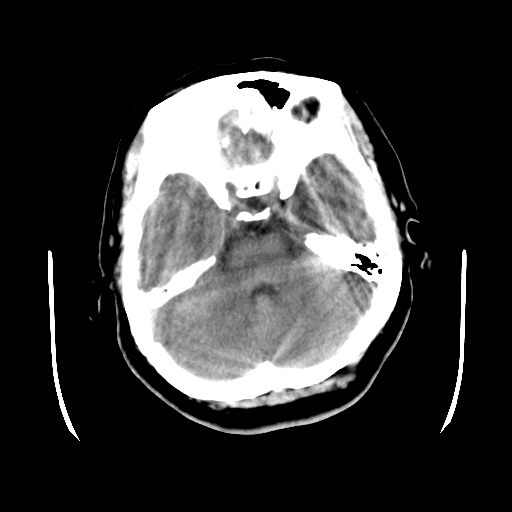

以下是引用cgf在2010-1-3 17:53:00的发言:[br]此病例多考虑:透明隔发育异常 透明隔囊肿可能性大;右侧基底节区(尾状核头)小片状低密度影考虑陈旧性腔梗[br][br]透明隔发育异常:包括透明隔间腔(第五脑室)、韦氏腔(第六脑室)、透明隔囊肿、透明隔缺如;前两者属于正常变异,后两者属于发育畸形;[br]透明隔间腔向下扩张形成韦氏腔;[br]有时透明隔间腔与透明隔囊肿很难鉴别;透明隔间腔间距一般不超过0.5cm,间距大于0.5cm时应考虑透明隔囊肿;[br]透明隔缺如为两侧脑室间隔缺如、融合成单脑室畸形,可伴有智力发育异常;[br][br]

以下是引用liaoqiang在2010-1-3 16:04:00的发言:[br]考虑侧脑室脉络丛囊肿?不除外变异的威氏腔。

以下是引用江广1996在2010-1-3 20:17:00的发言:[br]考虑变异的威氏腔。不除外侧脑室脉络丛囊肿.[br]透明隔囊肿大多数偏前,在侧脑室前角之间。